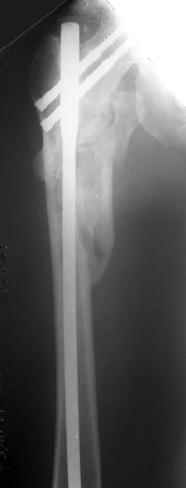

Наверно, можно и так сказать, но можно и тоже самое - 4-фрагментный вертельный перелом. Выбор тот же, но с учетом молодого возраста реконструкционный гвоздь тут более применим. Вот уже наш пример.

Перелом подвертельный. Лечение оперативное, срочное,

PFN с длинной ножкой чтобы избежать стрессовые изменения в будущем. Обычно у молодых людей требуется проводить рассверливание канала как при гвоздевании.

полную нагрузку через 6 недель т.е. после образования костной мозоли, что позволить более или менее сохранить длину шейки.